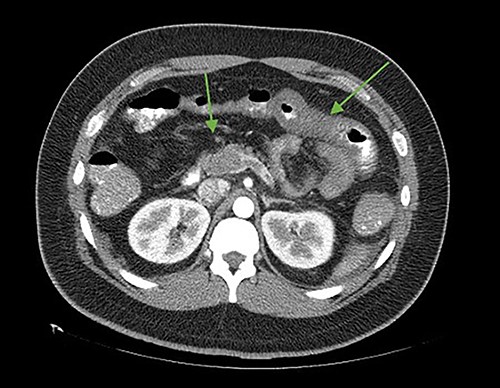

On the seventh postoperative day, he began with abdominal pain, tachycardia, fatigue, and anorexia, limited fluid intake and minimal ambulation. On the eighth day, the patient presented to the emergency department due to intolerance to oral feeding, acute abdominal pain (VAS 8/10), in antalgic position, tachycardic and diaphoretic. Physical examination revealed abdominal hyperalgesia and hyperalgesia. Laboratory tests revealed hemoglobin of 11 g/dl, 18 700 leukocytes (95.3% neutrophils), C-reactive protein of 13.3 mg/dl. Blood gases with pH 7.42, lactate 1.6 mmol/L. A contrast-enhanced abdominopelvic tomography showed portal, mesenteric, and splenic vein thrombosis associated with jejunal wall thickening with adjacent mesenteric changes and free fluid in the cavity (Figs 1 and 2).

Axial cut. In the arrows, lack of opacification of the portal vein with its hyperdense walls, inferior vena cava, lack of splenic opacity.